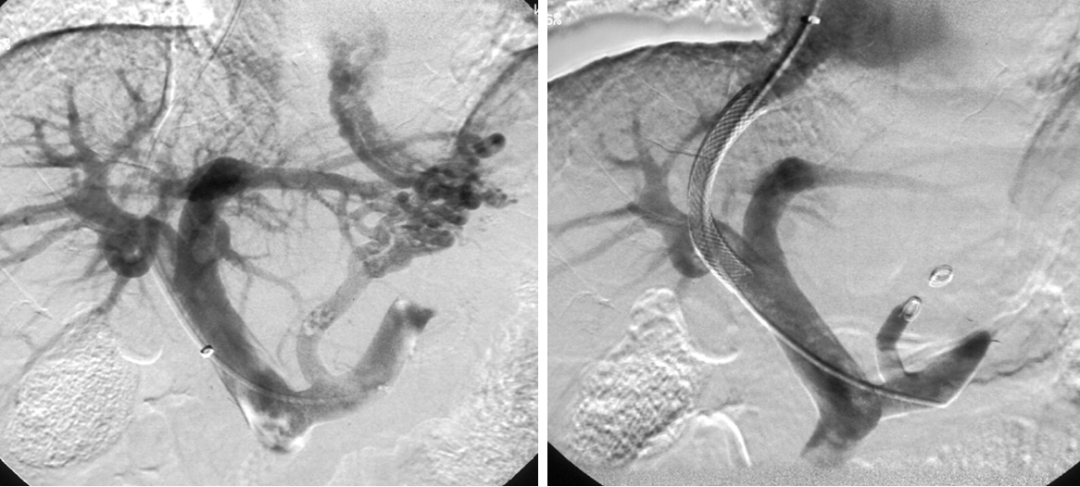

介入技术关键:精准诊断与个体化栓塞

出血造影直接征象:造影剂外溢;量小者需超选择插管造影证实;出血速度0.5~1.0ml/min。

出血造影间接征象:原发病的血管造影表现;局部血管异常聚集;血管痉挛、缺失;肿瘤染色;畸形血管团;动脉瘤……

图:造影剂外溢

图:A:空肠动脉畸形;B回盲部肿瘤染色:CD:胃十二指肠动脉瘤

图:十二指肠溃疡出血,腹腔干造影,未见外渗,超选胃十二指肠动脉造影见外溢